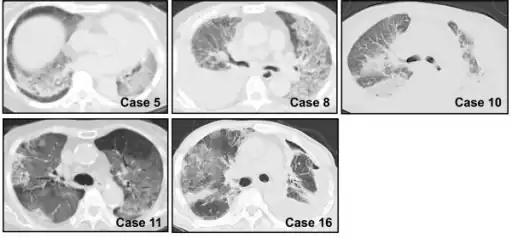

Chest CT images of five persons/cases who developed acute interstitial pneumonia